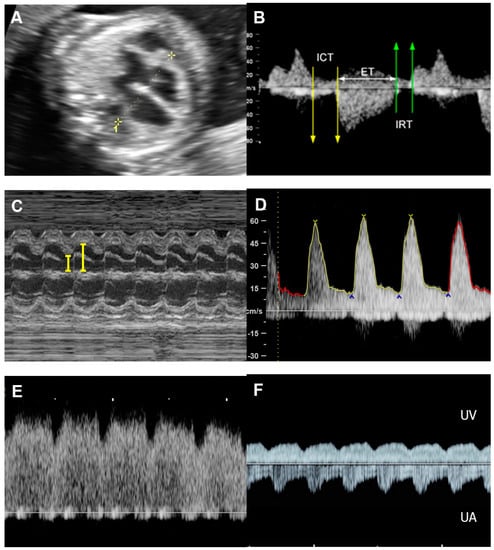

| Parameters | Abnormal Changes | Interpretation |

|---|---|---|

| Dimension | ||

| Cardiothoracic area ratio | Increased >35% | Cardiac enlargement |

| Cardiothoracic diameter ratio | Increased >95th centile | Cardiac enlargement |

| Inflow characteristics | ||

| Filling time fraction | Decreased | Diastolic dysfunction |

| E/A ratio | Monophasic | Diastolic dysfunction |

| Decreased | Diastolic dysfunction | |

| Increased | Volume loading/External compression | |

| Venous PW Doppler | ||

| Inferior vena cava | Reversed A-wave >20 cm/s | Diastolic dysfunction /increased venous pressure |

| Decreased S-wave | Tricuspid regurgitation | |

| Ductus venosus | Absent or reversed A-wave | Diastolic dysfunction/increased venous pressure |

| Performance | ||

| Shortening fraction | Decreased (<28%) | Systolic dysfunction |

| Increased | Reduced afterload/increased contractility | |

| Ejection fraction | Decreased <50%) | Systolic dysfunction |

| Cardiac output (Stroke volume) | Decreased (Z < −2) | Systolic dysfunction/poor filling |

| Increased (Z > +2) | Reduced afterload/volume load | |

| Tei index | Increased > 0.50 | Global cardiac dysfunction |

| ICT: 28 (22–33) ms | Prolonged | Systolic dysfunction |

| IRT: 34 (26-41) ms | Prolonged | Diastolic dysfunction |

| Systolic strain/Strain rate | Increased | Reduced afterload |

| Decreased | Reduced contractility | |

| E/Vp (Color M-mode) | Increased | Diastolic dysfunction |